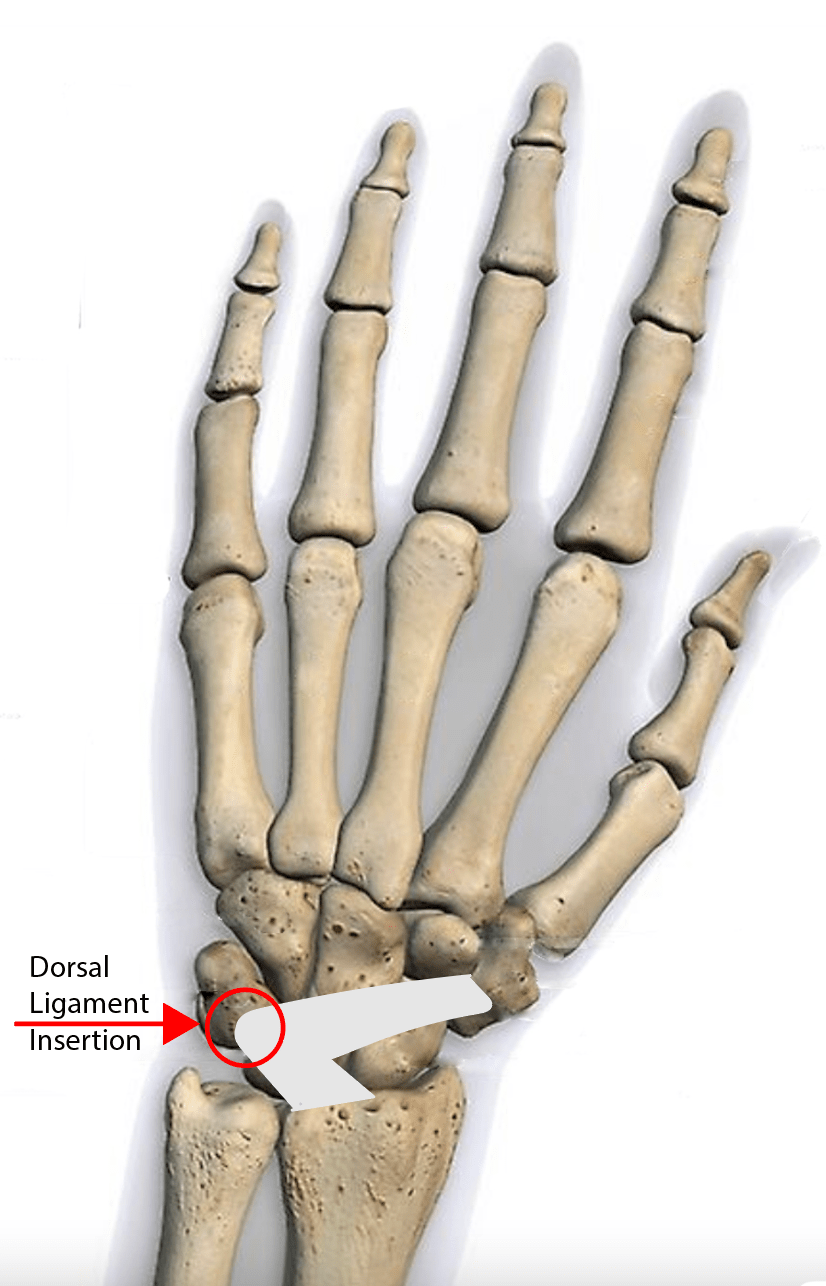

Avulsion Injuries of the Hand and Wrist RadioGraphics Triquetrum Fracture X Ray A triquetrum with a normal appearance. Although they are usually managed. Triquetrum fractures are common carpal fractures that are often associated with other injuries to the wrist. Diagnosis is confirmed with orthogonal views of the wrist. Triquetrum fractures typically occur from a fall onto an outstretched arm with the wrist in extension and ulnar deviation, or in extreme. Triquetral fractures. Triquetrum Fracture X Ray.